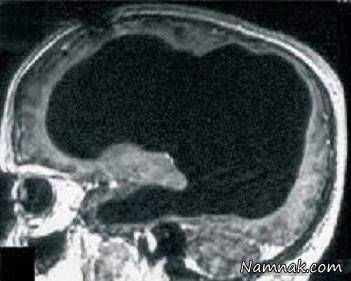

او به دلیل ضعف اندکی که در پای چپش حس می کرد به دکتر مراجعه کرد و پس از اینکه اسکن مغز بر روی انجام شد، تصاویر نشان می دادند که جمجمه او اکثر با مایعی پر شده است. اسکن مغز این شخص نشان می داد که تنها یک لایه نازک از بافت واقعی مغز باقی مانده و بخش داخلی مغز او تقریبا به طور کامل از بین رفته است. عکس زیر، اسکن مغزی این شخص را نشان می دهد: